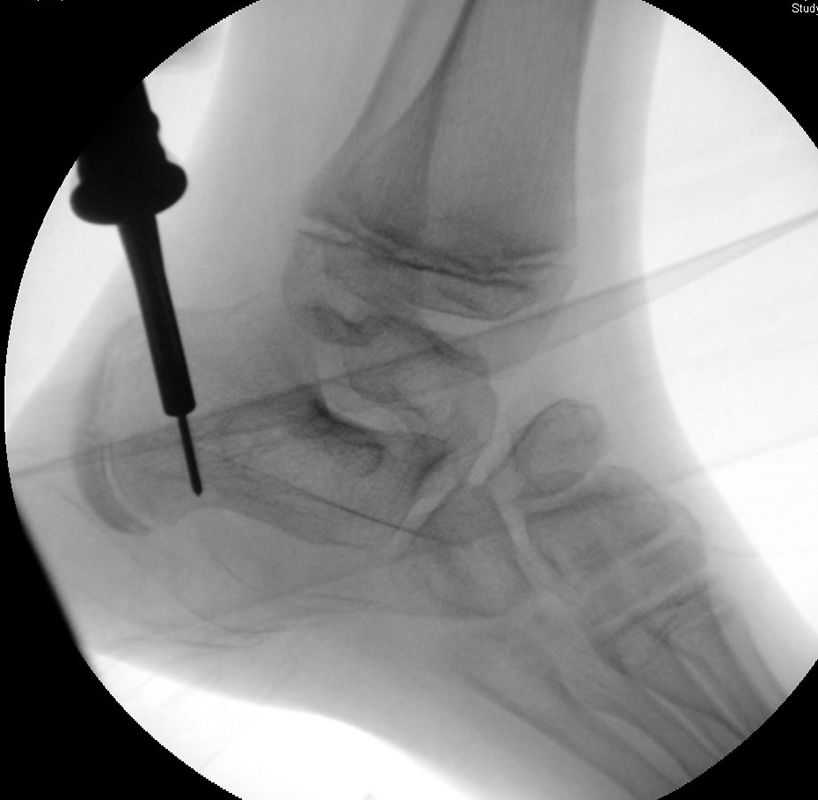

Calcaneus-Osteotomie

Die minimalinvasive Calcaneusverschiebeosteotomie bietet eindeutige Vorteile gegenüber dem offenen Verfahren, sodass wir bei Kindern und Jugendlichen nahezu keine offene Verschiebeosteotomie mehr durchführen. Am Calcaneus liegt die offene Wachstumsfuge dorsal. Bei der Durchführung müssen Schenkel der V-förmigen Osteotomie daher etwas steiler angelegt werden, in einem stumpfen Winkel (siehe Abb. 3 a-j). Für die Osteotomie liegen unsere Patienten auf dem Rücken und der BV wird für die exakte Seitaufnahme eingestellt. Der Fuß lagert auf einem hohen OP-Kissen und die Osteotomie kann bequem mit einem langen Kirschner-Draht und einem sterilen Stift angezeichnet werden (Abb. 15).

Abb. 3 a-j: Beispiel einer Calcaneusverschiebeosteotomie mit offenen Wachstumsfugen und der entsprechenden Osteosynthese mit Kirschner Drähten. Lokalisation der Osteotomie (a), Lage der Fräse (b-d), Drahtlage mehrere Ansichten (e-h), Heilung der Osteotomie 4 Wochen postoperativ und Entfernung der Drähte (i-j).